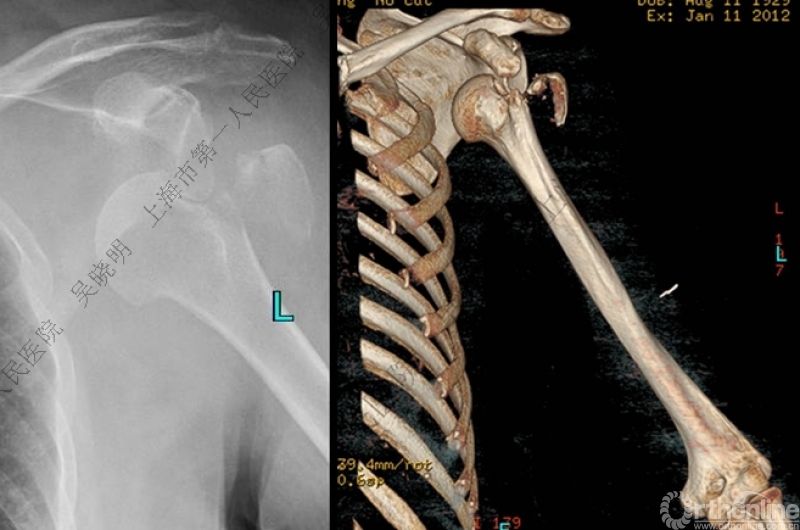

下图考虑为孤立性的大结节骨折?

看完片子,你会发现高质量的平片甚至3D CT也难以发现

X线看不清骨折线,三维CT也看不清